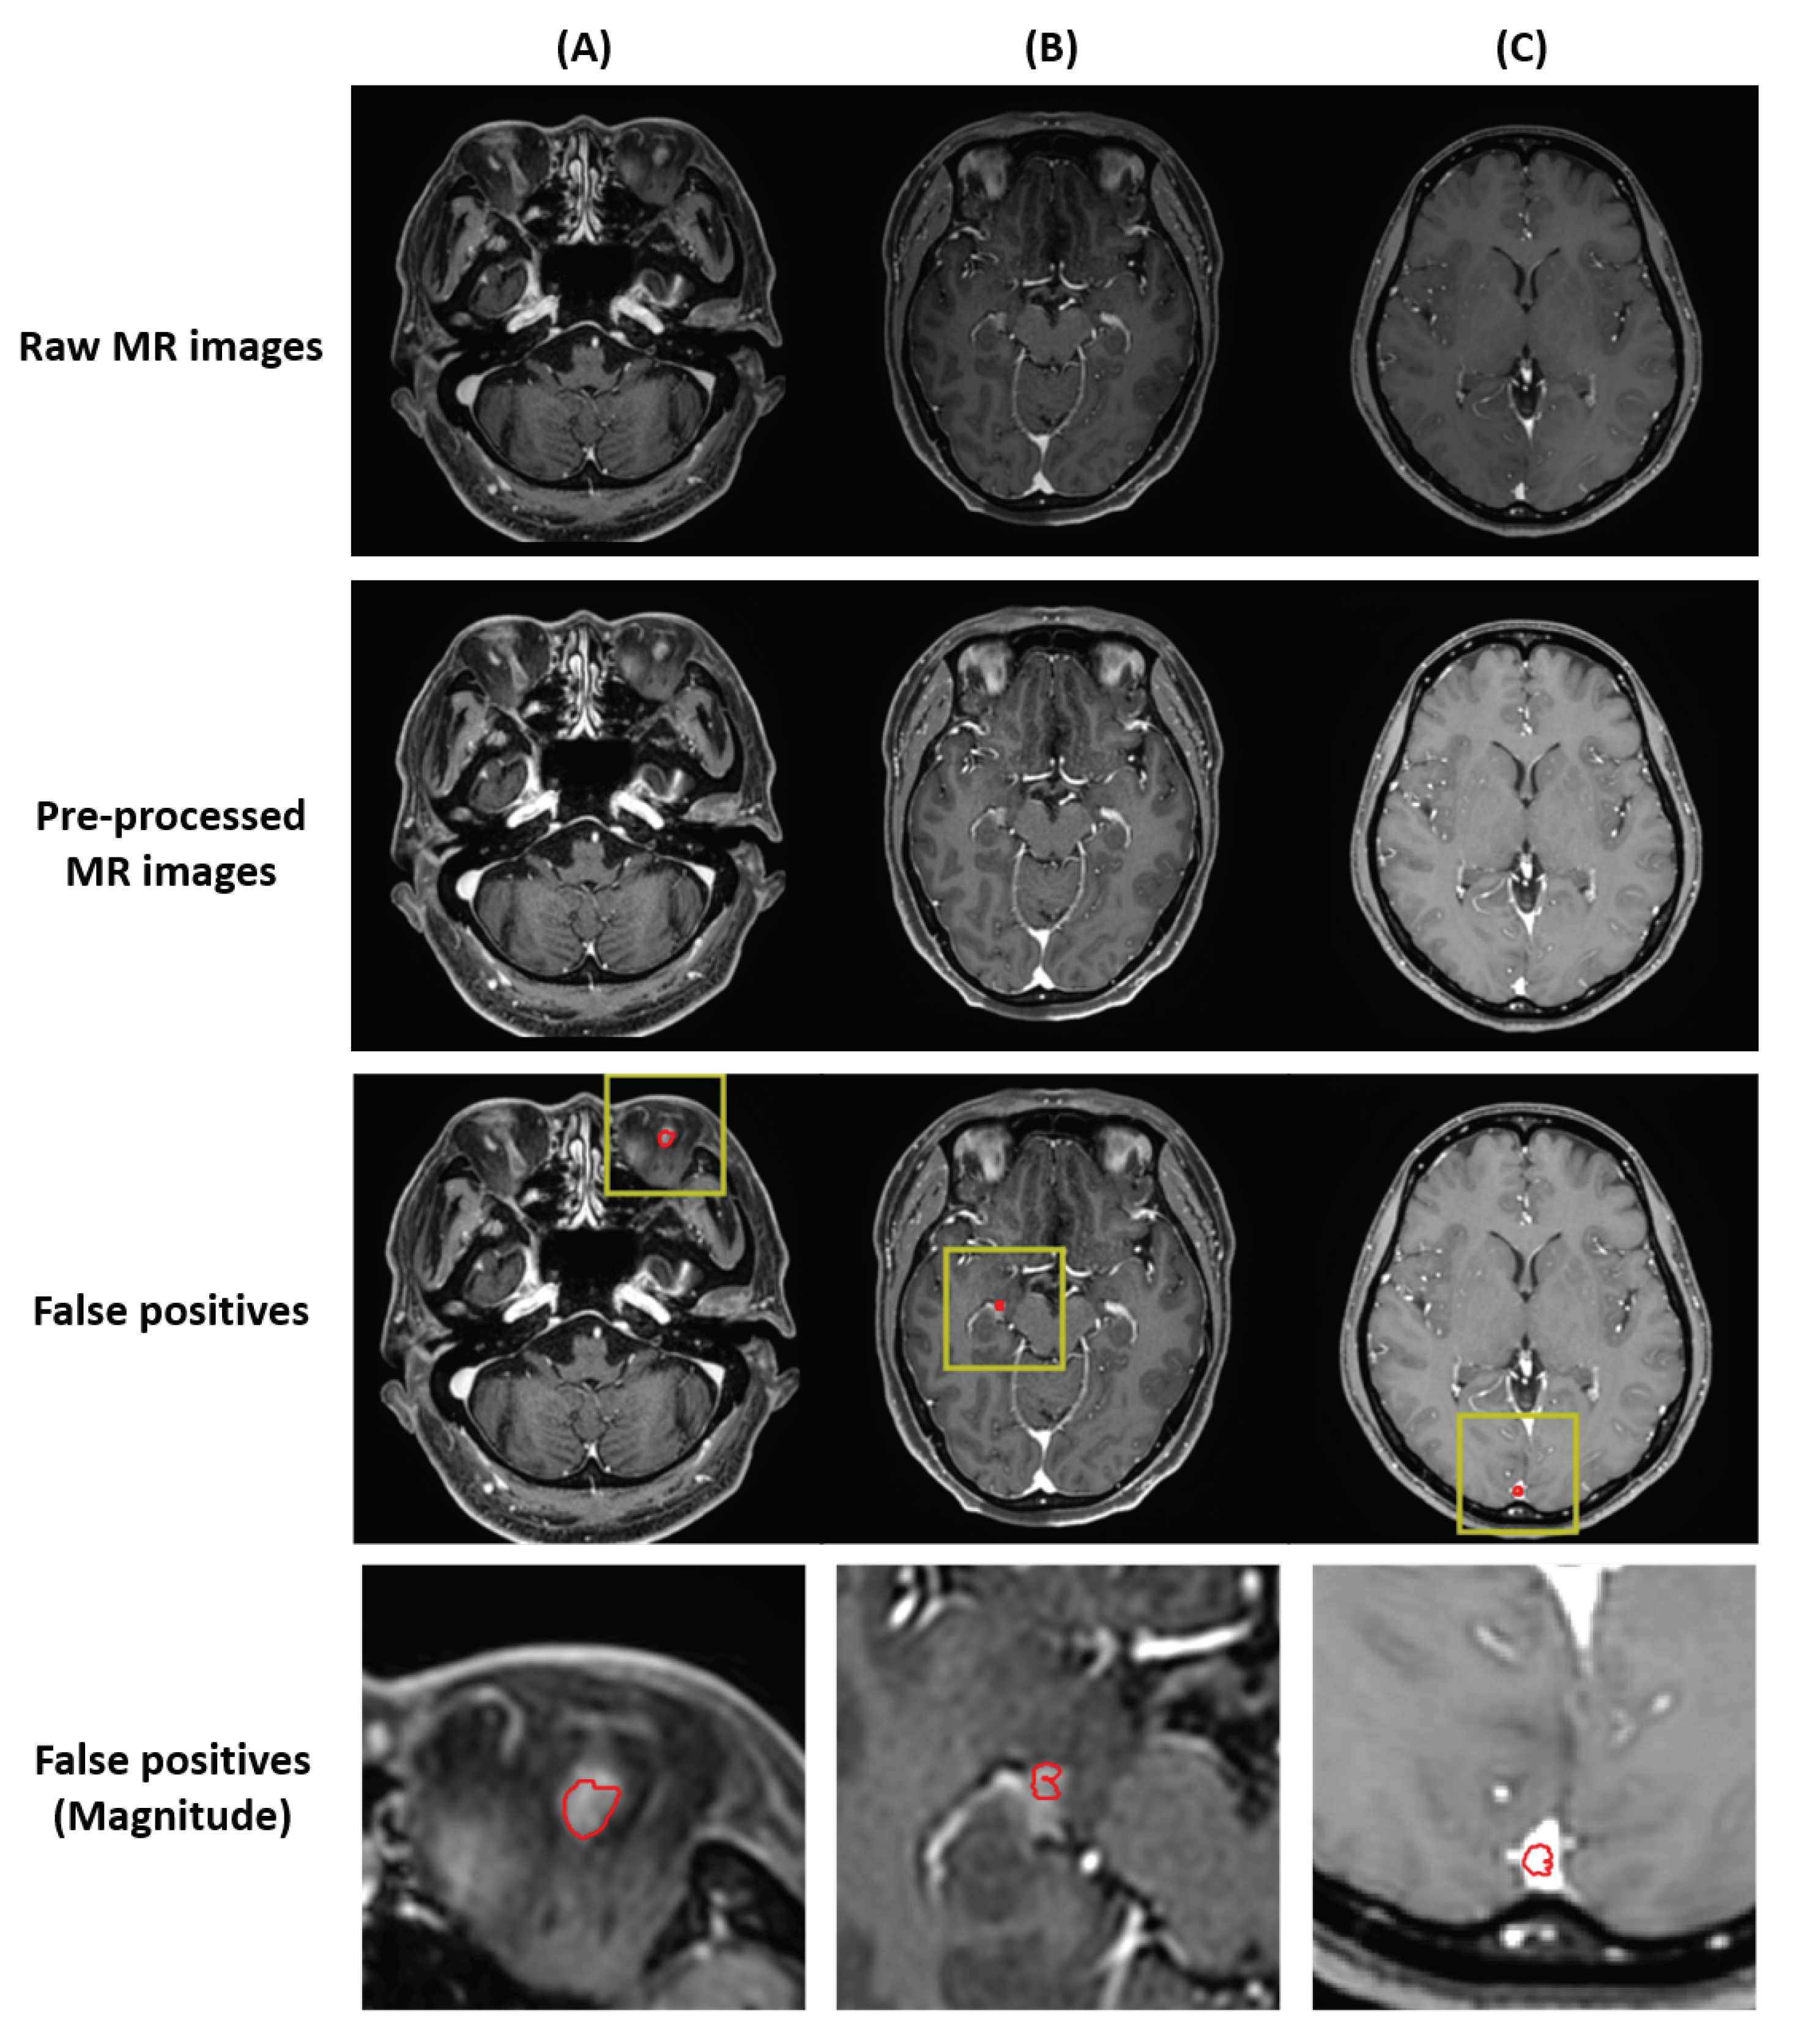

The locations of false positives can be summarized in three ways (Figure 4). First, the false positives were found outside the brain structure. Second, the false positives were found in a structure with high intensity. Third, the false positives were found in the superior sagittal sinus.

Figure 4. Locations of the false positives. (A) Delineation created outside the brain; can be solved with skull-stripping. (B) Delineation created in a structure with high intensity; can be solved with extensive gamma correction. (C) Delineation created in the superior sagittal sinus; can be solved with black-blood sequencing. In each images, red in the yellow bounding box indicates false positives.